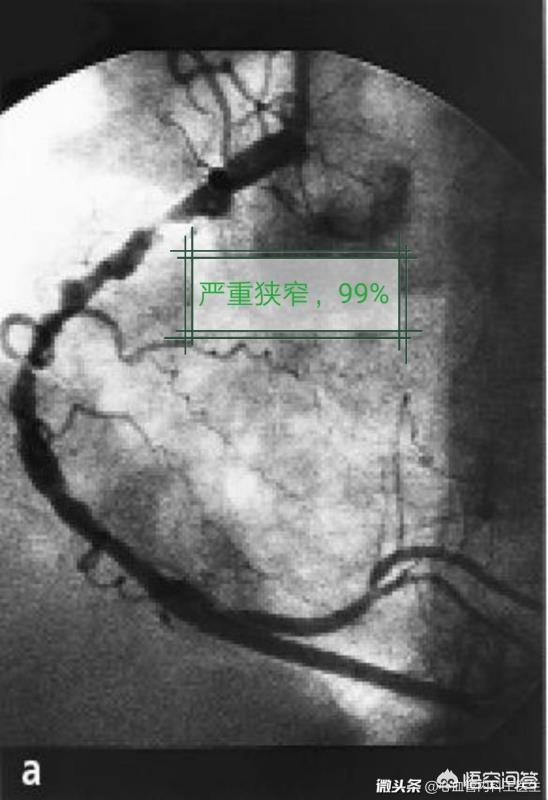

1、ブランクステント(ベアメタルステント):ステントは人体にとって異物であり、人体はそれを「攻撃」し、内皮細胞の過形成や炎症反応を起こし、平滑血管の再狭窄や閉塞を引き起こす可能性がある。空ステントの再狭窄や閉塞の発生率は30%と高く、現在では使用されていない。

2、薬剤ステント:心臓ステントを留置した後の閉塞をさらに防ぐために、金属ステントの表面に薬剤の膜をコーティングしたものが薬剤ステントである。この種のステントは体内に留置された後、薬剤がゆっくりと放出され、ステント周囲の瘢痕組織の増殖を抑制し、冠動脈の開通を維持する。これにより、冠動脈の再狭窄や閉塞の発生率は10%に減少する。

ステント内再狭窄はステントを留置した血管は、より長い期間(通常は数カ月から数年)をかけて、ゆっくりと再び閉塞していきます。このプロセスは非常にゆっくりなので、通常は心臓発作には至らず、最も一般的な症状は狭心症です。

現在のデータでは、ステント内再狭窄の5年発生率は全体で約10%である。